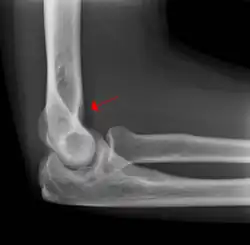

In addition to fracture, any process resulting in an elbow joint effusion may also demonstrate an abnormal fat pad sign. Increased intracapsular fluid is also seen in several conditions other than fracture and this produces the abnormal fat pad sign. (toxic synovitis, septic arthritis, Juvenile Rheumatoid Arthritis, osteomyelitis of the distal humeral physis and secondary septic joint). In these instances, history and clinical examination in addition laboratory results (WBC, ESR, CRP) will guide the provider in determining whether to treat the condition as an occult fracture or continue workup for other pathology.

The fat pad sign is invaluable in assessing for the presence of an intra-articular fracture of the elbow. An anterior fat pad is often normal. However a posterior fat pad seen on a lateral x-ray of the elbow is always abnormal. The patient will be unable to flex their elbow and requires orthopaedic input.[2]